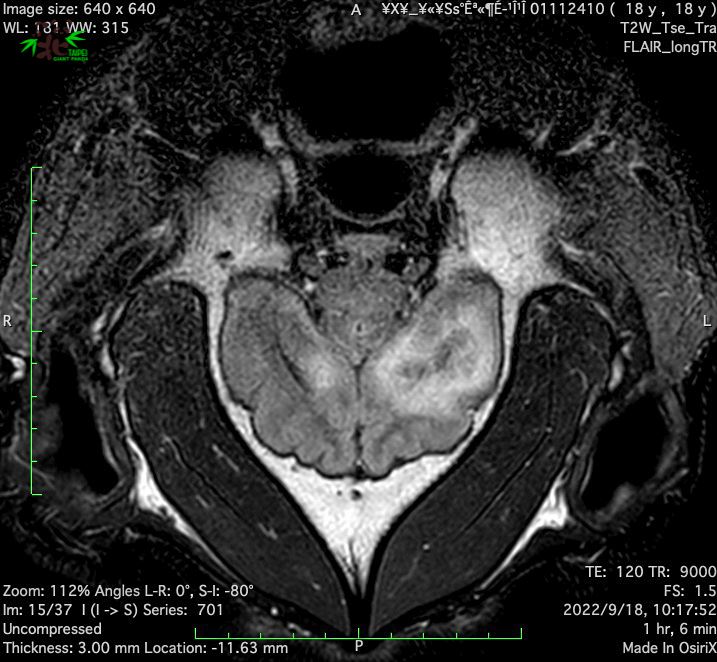

月18日上午载著「团团」及工作人员的车队离开动物园,于8:49到达台大附设动物医院,随后为「团团」进行麻醉,再进行脑部MRI检查。MRI影像显示「团团」左大脑半球有局部液化坏死病变,右大脑半球亦可见类似病变,此病变可能是造成团团癫痫发作的原因。为进一步厘清脑部病变的可能肇因,兽医师为「团团」采取脑脊髓液进行后续的分析化验,也同时完成整体生理检查。

「团团」MRI检查影像。动物园提供